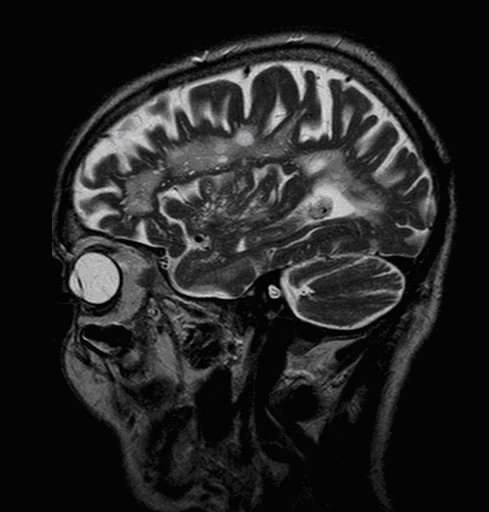

On MRI, diffusion restriction causes hyperintense signal on T2W images. The leptomeningeal border of the infract zone will show contrast enhancement.

Multiple sclerosis typically appears with lesions presenting in the hemispheric white matter with a periventricular predilection. Other less usual locations for MS lesions include the cerebellum and the pons.

The method of choice for the imaging of multiple sclerosis is MRI. MS lesions secondary to their increased water content appear as increased signal intensity lesions on (T2 weighted), PD images and on FLAIR sequence.